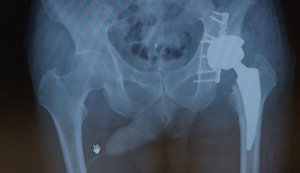

初期治療を施したX線

人工股関節を用いた再建術後のX線